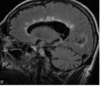

What type of herniation is depicted by the arrow? [1] Uncal Central (transtentorial) Cingulate (Subfalcine) Transcalvarial Upward cerebellar (transtentorial) Downward cerebellar (Tonsillar)

**Uncal** Central (transtentorial) Cingulate (Subfalcine) Transcalvarial Upward cerebellar (transtentorial) Downward cerebellar (Tonsillar)